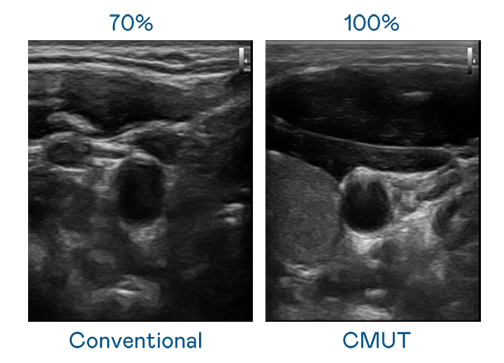

CMUT 技术是一种用电容式微机电元件来产生超音波讯号的技术。与传统 PZT 压电式技术相比,CMUT 频宽增加 30%,更宽频的超音波讯号让影像解析度大幅提升,是实现高影像品质医疗超音波扫描、促进精准医疗发展的关键技术。

超音波影像的解析度高低,首先取决于探头能发出的讯号频宽。冰球突破 CMUT 可提供高清晰的超音波讯号,提供高频宽、高灵敏度、影像纹理细节更高的超音波影像,协助医护人员缩短影像判读时间及利用精准的医疗影像进行诊断。